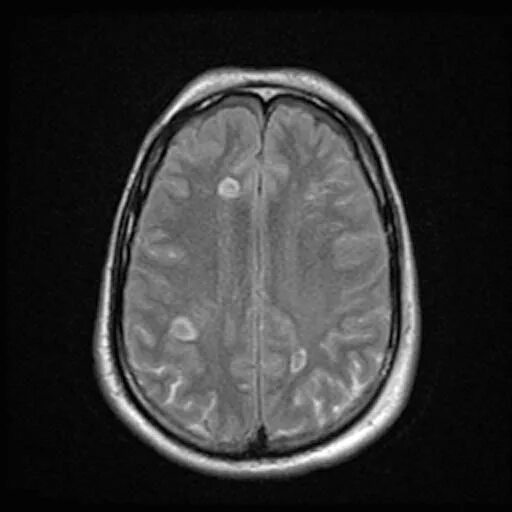

Диффузные повреждения